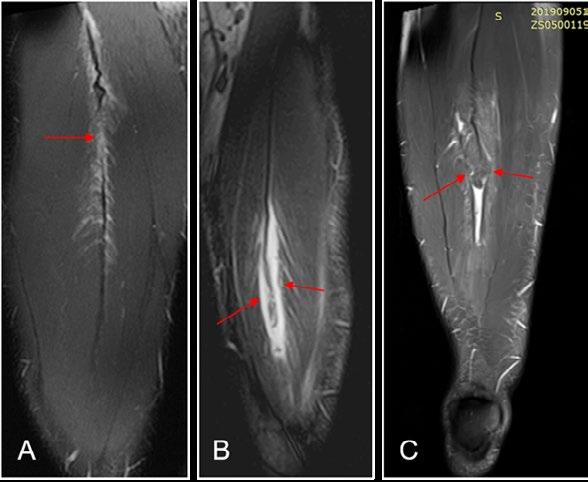

Figure 1: Reproduced from Entwisle et al. The anterolateral epimyseal surface of the long head (L) condenses to form the proximal portion of the distal musculotendinous junction. The opposing epimyseal condensations at the anterolateral aspect of the long head (L, large arrow) and the posterolateral aspect of the short head (S, small arrow) form the midportion of the distal musculotendinous junction that appears T-Shaped.

T-Junction Injuries

It is not just intramuscular tendon injuries that have particularly high re-injury rates. Consideration needs to be given also to the distal hamstring, which may have its own characteristics. Kenneally-Dabrowski, et al. 12 noted that amongst a group of professional rugby players, distal hamstring injuries were the injuries typically classified as more severe. Entwisle, et al. 13 was the first to describe what is now known as the T-Junction of the distal hamstring. This is the confluence of the epimyseal surfaces of the biceps femoris long head and short head (Figure 1). These authors report re-injury rates for this sub-type of hamstring injury at 70% for the higher grade injuries, which must be the highest reported re-injury rate for any muscle injury. 13 Similarly, Kayani, et al. 14 noted 55% recurrence rates from conservatively managed injuries to this area. Shamji, et al. 7 in their group of professional footballers at Aston Villa found that most of the re-injuries they had, were indeed in the region of the T-Junction.

Figure 2: Distal Biceps Femoris (T-Junction) injury during a braking and rotation task. Reproduced from Kerin et al. (2022)

MRI is the probable imaging type of choice to confirm diagnosis, although dynamic ultrasound is also useful. Synchronous movement of the short and long heads during an isometric prone curl can be assessed and monitored as either a prognostic or progress indicator, though a reliable and valid protocol has yet to be described.